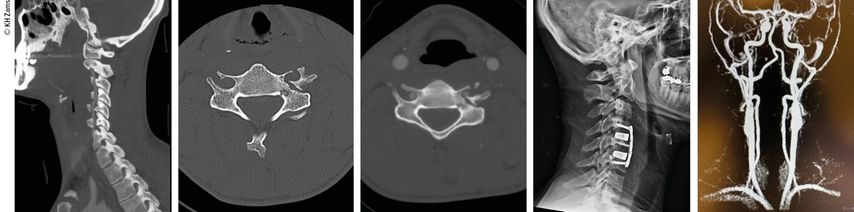

Der interdisziplinäre Ansatz ist entscheidend. Liegt beispielsweise eine instabile HWS-Verletzung mit Vertebralis-Dissektion vor, so ist die Wiederherstellung stabiler Verhältnisse für u.a. die A. vertebralis vordergründig (Abb.2–4). Dieser operative Eingriff erfolgt bereits unter therapeutischer Heparinisierung. Je nach Ausmaß der Gefäßverletzung wird dabei ein- oder zweizeitig die endovaskuläre/offene Therapie zur Gefäßreperfusion durchgeführt. Aktuelle interdisziplinäre Therapieempfehlungen:

Abb. 4: Mann, 28a, Z.n. Schisturz; instabile Teardrop-Verletzung mit Dissektion A. vertebralis l.; Zervikobrachialgie mit Dysästhesie C6, mehrere kleine embolische Infarkte vertebrobasilär mit Koordinationsstörung; OP + Heparintherapie initial, anschließend APT